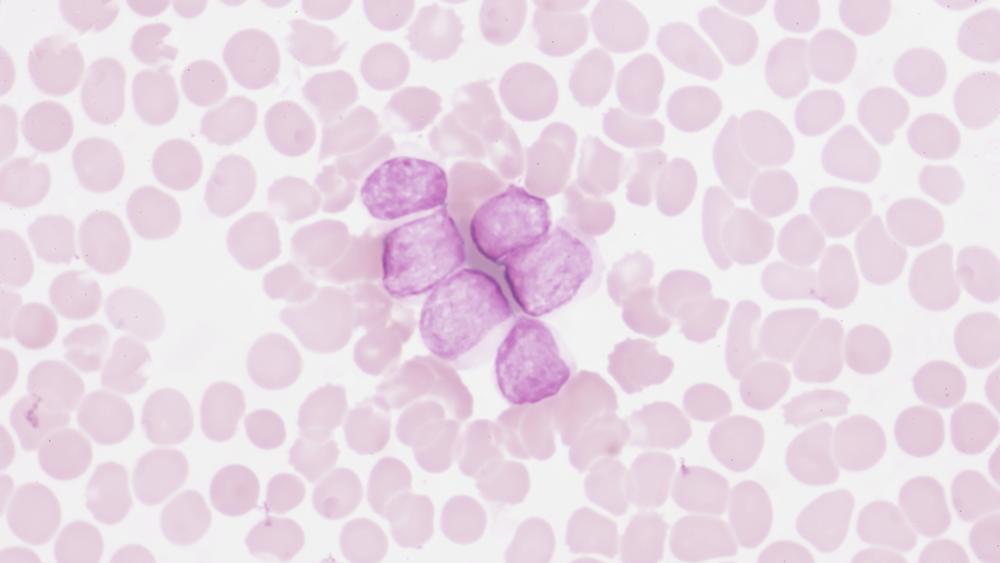

Хронические лейкозы

Это клональное опухолевое новообразование, которое обусловлено злокачественным перерождением ранних гемопоэтических (кроветворных) клеток и характеризуется постепенным распространением и разрастанием атипичных клеток.